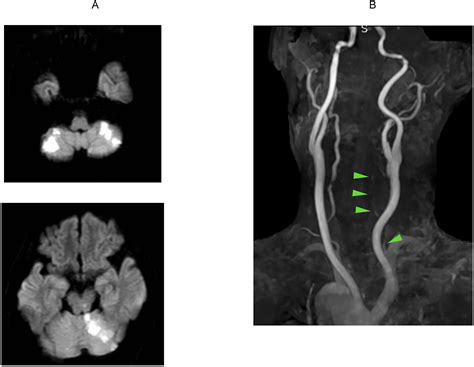

• CT Angiography (CTA): This provides a detailed 3D view of the blood vessels in the neck and brain, identifying blockages quickly.

• Magnetic Resonance Angiography (MRA): Useful for visualizing blood flow without the use of ionizing radiation.

• Digital Subtraction Angiography (DSA): Considered the "gold standard," this invasive procedure involves injecting contrast dye to map the arteries with high resolution.